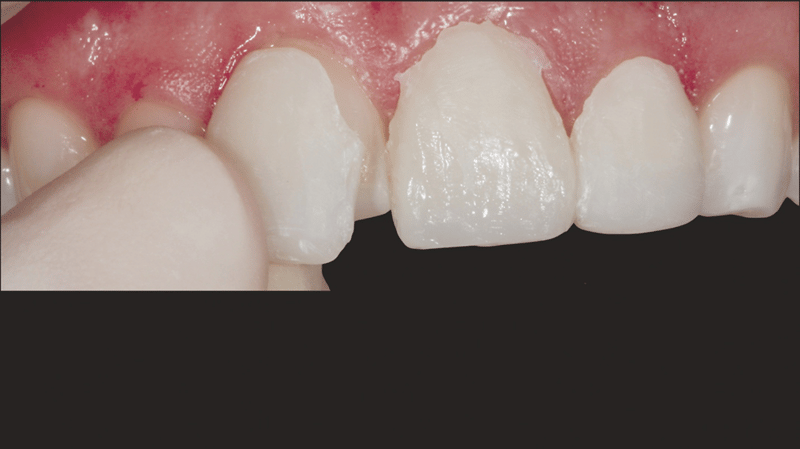

- Komposit-Applikation: Applikation von Transcend Komposit (Farbe B1D ), beginnend mit einem 2/3 Abstand von der Inzisalkante. Allmähliche Ausdünnung in Richtung Gingiva. Applikation der Farbe „Universal Body“ (UB) nahe des gingivalen Drittels. Auftragen der finalen Schichten mit Enamel White (EW) und einer kleinen Menge UB am gingivalen Rand, um einen natürlichen Farbverlauf zu erzielen.

- Konturierung der Ränder: Konturierung der Ränder mit einem feinen Mosquito-Diamantbohrer zur gewünschten Form.

- Faziale Anatomie: Verwendung von kugelförmigen und langen, dünnen Diamantbohrern zur Ausgestaltung der fazialen Anatomie. Erstpolitur mit Jiffy™ Natural Polierern. Hochglanz-Finish zum Erhalt der tertiären Anatomie mit Ultradent™ Diamond Polish Mint und Jiffy™ Goat Hair Brush (in Europa nicht verfügbar).